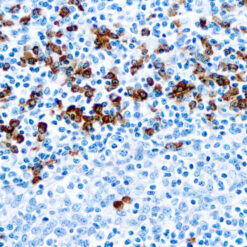

Synaptophysin (SYP02)

This antibody isspecific to a 38 kDa protein. Synaptophysin is an glycoprotein occurring in presynaptic vesicles of neurons in the brain, spinal cord, retina, vesicles of adrenal medulla and in neuromuscular junctions. This antibody reacts with neuroendocrine neoplasms of neural as well as epithelial types.

| Cellular Localization | Cytoplasmic |

| Positive Control Tissue | Pancreas |